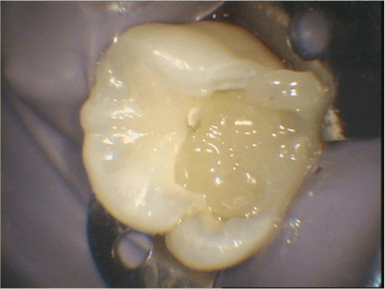

Par comparaison, quelques photos de coiffage pulpaire au CO²

et fin